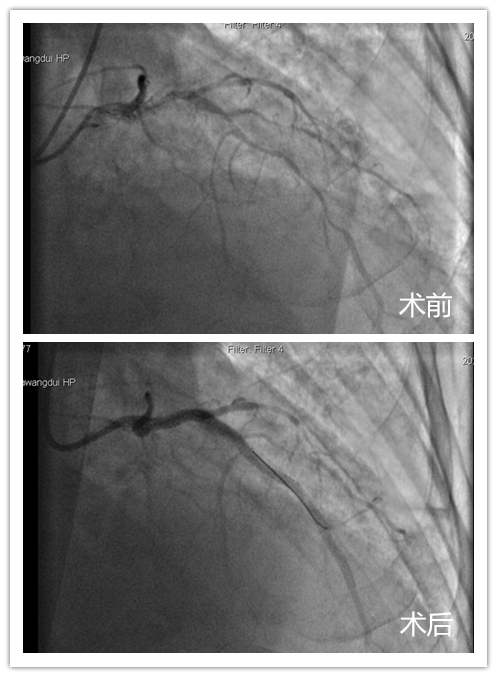

经冠脉造影提示,李嗲嗲心脏三根大血管均有病变,其中左前降支出现了95%严重狭窄,且血管有明显钙化扭曲。由于患者高龄,合并高血压、糖尿病,心衰和肾功能差,同时存在主动脉严重狭窄,为高危复杂冠脉病变,手术难度非常大。在郑主任主持下,潘宏伟主任、董波主任、容志毅主任与心内四科医生再次讨论李嗲嗲病情,制定了手术方案,并决定在马王堆院区完成这例高难度复杂介入手术。

330,在两院区介入心内科专家团队通力协作下,顺利为李嗲完成了手术。术后,患者病情稳定,胸闷气喘明显好转。48日,在经过一周多精心护理后,患者即将康复出院。